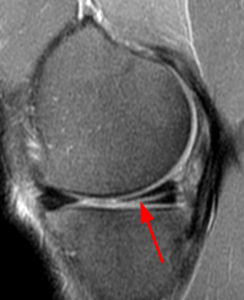

MRI scan: is vaak het aangewezen onderzoek om een meniscus scheur in beeld te brengen.

Klinische test voor meniscusletsel - McMurray test MRI-beeld van een meniscusscheur